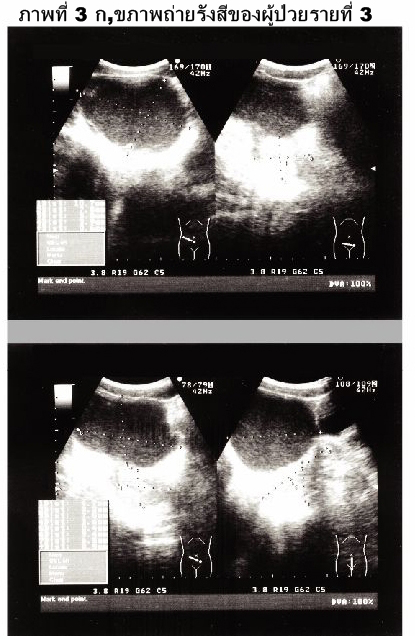

หญิงไทยโสดอายุ 20 ปี มีประวัติปวดประจำเดือนทุกเดือน อาการปวดเป็นมากขึ้นเรื่อยๆ จน ต้องกินยาแก้ปวดโดยเพิ่มปริมาณและชนิดของยามากขึ้น. การตรวจทางรังสีปรากฏลักษณะดังภาพที่ 3ก,ข.

1. Ultrasonogram ของช่องท้องส่วนล่าง.

2. เงาพยาธิสภาพคล้ายถุงน้ำในอุ้งเชิงกรานด้านขวาอยู่หน้ามดลูก.

3. ผลการตรวจทางรังสีร่วมกับประวัติ dysmenorrhea ที่รุนแรงขึ้นอย่างต่อเนื่องบ่งชี้ภาวะ endome-trioma.

4. เนื้องอกของรังไข่ชนิดเป็นถุงน้ำโดยอาจเป็น dermoid ในหญิงวัยสาว ซึ่งมักมีส่วนของไขมันหรือกระดูกร่วมด้วย แต่ในผู้ป่วยรายนี้ไม่มี.